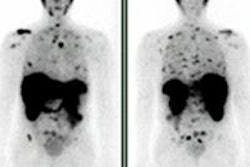

To be held on 5 March at the Austria Center in Vienna, the course will be a forum for radiologists, radiation oncologists, and surgical oncologists to deepen their knowledge on the use of imaging in a multidisciplinary environment. It will provide education on imaging in the diagnosis and treatment of rectal, prostate, cervical, and breast cancers, according to ESOR.